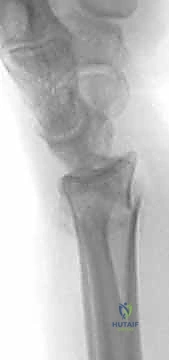

* تشوه شكل الرسغ: يُعرف كلاسيكياً بـ "تشوه ظهر الشوكة" (Dinner Fork Deformity)، حيث ينزاح الجزء المكسور من الكعبرة نحو الخلف (الناحية الظهرية)، مما يعطي الرسغ شكلاً يشبه ظهر الشوكة.

2. الأشعة السينية (X-rays): وهي الفحص الأساسي لتأكيد الكسر، وتحديد مكانه، ومدى الإزاحة والتفتت.

3. الأشعة المقطعية (CT Scan): في الكسور المعقدة والممتدة داخل المفصل، يطلب الدكتور هطيف أشعة مقطعية ثلاثية الأبعاد لبناء تصور دقيق لسطح المفصل، مما يساعد في التخطيط الجراحي لوضع الشريحة الظهرية بدقة متناهية.